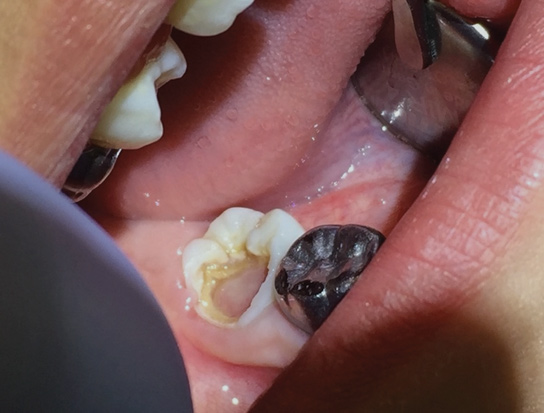

(2.) Bitewing radiograph of tooth No. 18 with radiographic evidence of distal carious defect. This tooth tested within normal limits to cold sensibility tests. Under the current diagnostic terms, the pretreatment pulpal diagnosis would be asymptomatic irreversible pulpitis.

Figure 2

These findings demonstrate that the pulpal diagnostic term asymptomatic irreversible pulpitis needs to be updated. This diagnosis represents a tooth that presents with clinical and radiographic evidence of caries (Figure 2) and responds normally to clinical sensibility testing to cold. The AAE Consensus Conference Recommended Diagnostic Terminology defines asymptomatic irreversible pulpitis as "a clinical diagnosis based on subjective and objective findings indicating that the vital inflamed pulp is incapable of healing. Additional descriptors: no clinical symptoms but inflammation produced by caries, caries excavation, trauma."12 In reality, this diagnosis can technically only be confirmed histologically. But, according to the results of the study conducted by Ricucci and colleagues13, teeth that responded normally to cold testing demonstrated only a mild to moderate accumulation of chronic inflammatory cells beneath the tubules that were affected by caries, and the inflammation did not extend through the entire portion of the pulpal tissue. Therefore, the pulp of a carious tooth that responds normally to cold testing should be diagnosed as normal pulp, not asymptomatic irreversible pulpitis. A more pertinent use of the diagnostic term asymptomatic irreversible pulpitis would be for cases involving a pulp polyp or internal resorption of a vital tooth (Figure 3).